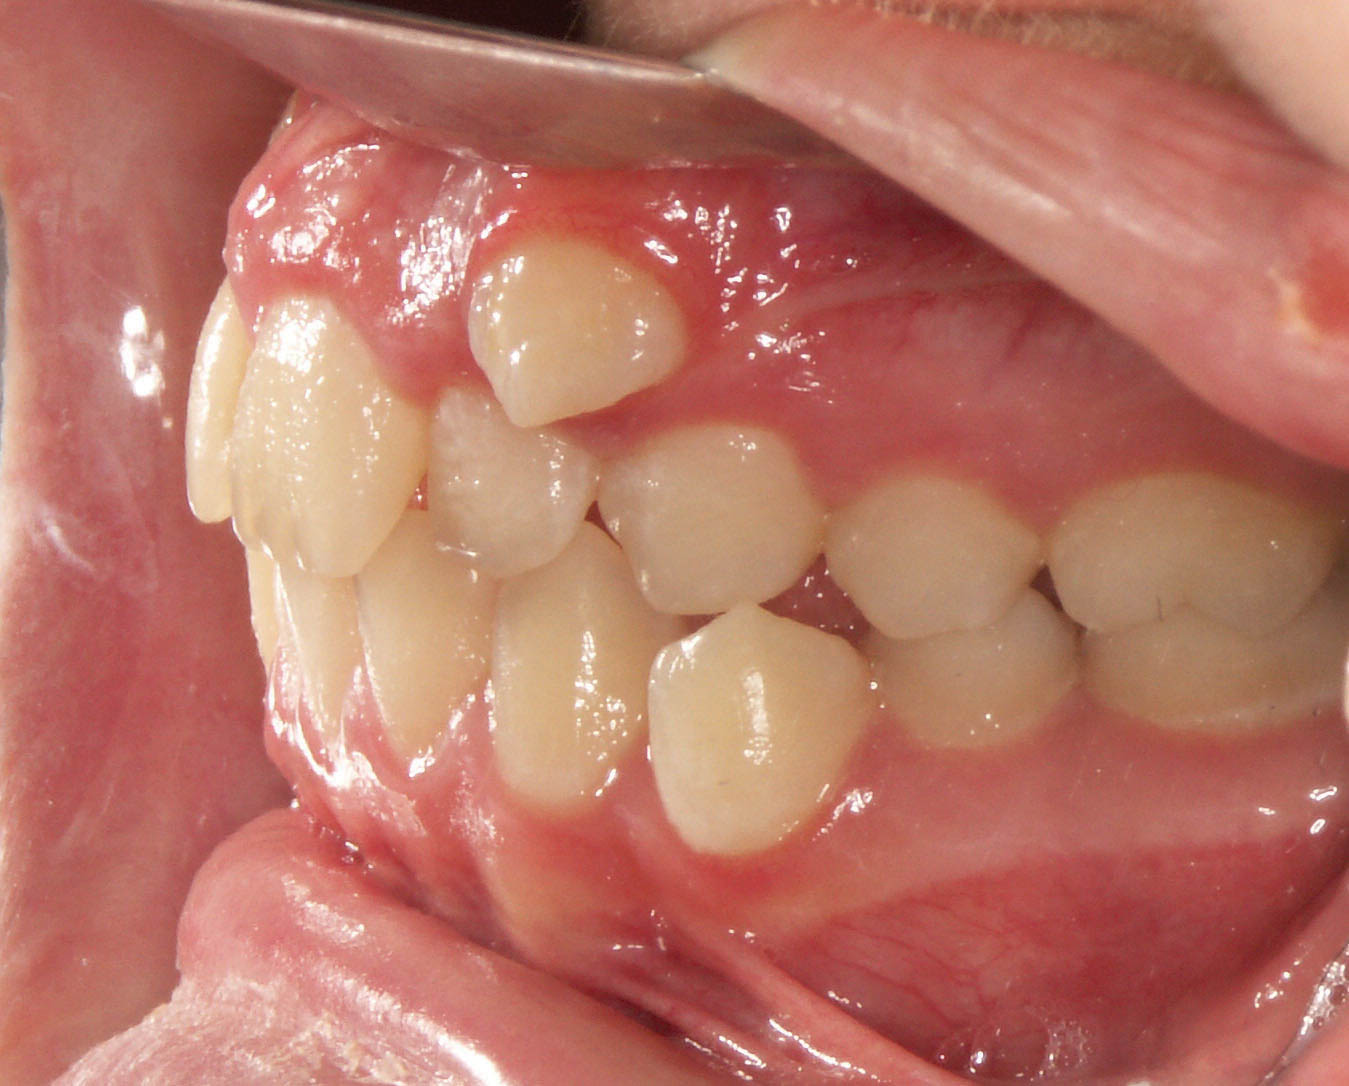

شکل 107-2: اکلوژن یک کاسپ کامل کلاسII در سمت راست